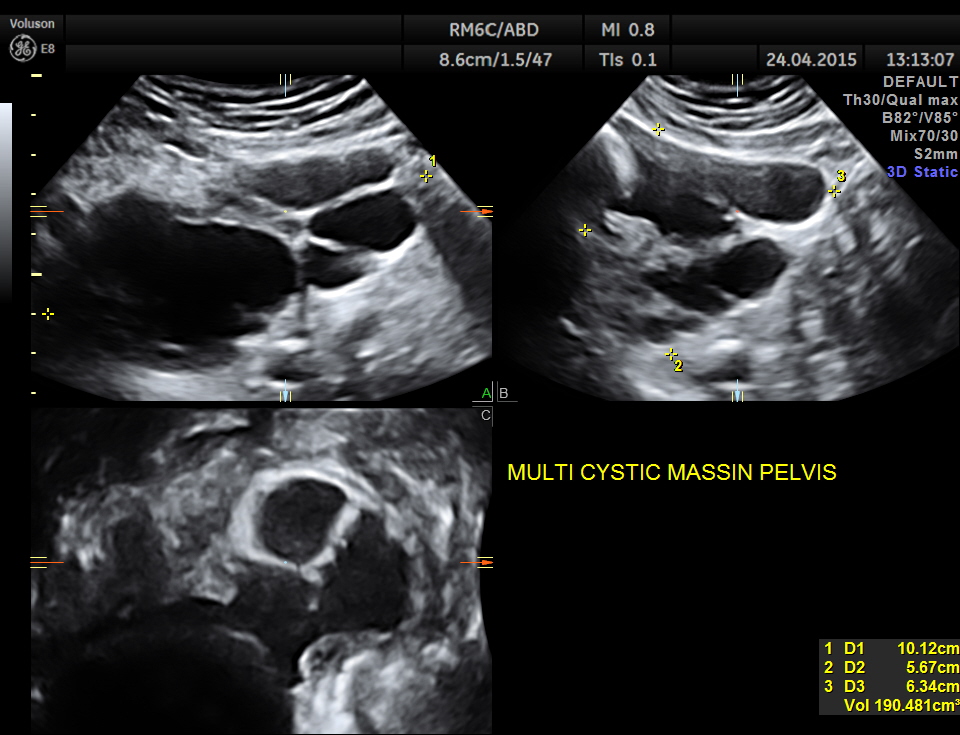

Scan of the urinary bladder in a more cephalic angle shows the following :

Superior angling shows a multi cystic pelvic mass – ? bladder diverticulae